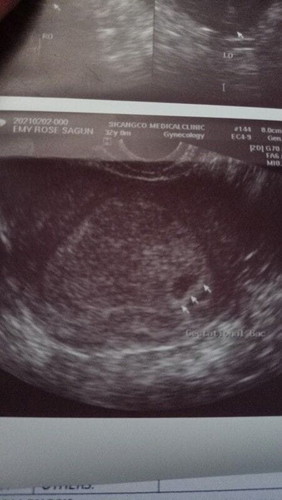

5wks ako nun 1st ultrasnd ko,after 2wks check uli, lumki lng konte gs at 5wks parin,ok lng kaya un

After 2wks 5weeks parn

as long as walang masakit at di ka dinudugo relax ka lang. ako nga nagpaultrasound at 6 weeks sabe nung OB wala pa daw heartbeat e nakikita ko nagfliflicker yung sa monitor. tas inulit nya ayun nakita nya. onga may heartbeat na sabe nya. minsan nakakawala ng tiwala e. kaya trust your body and instinct. and don't forget to pray always. ❤

minsan kasi mahirap talaga sila imeasure dahil nga maliit pa. di naman kasi accurate ang ganyan lalo na hindi marunong naguultrasound. ichill mo lang momsh at wag maistress.

thank u po❤️ sa totoo lng nalulungkot na ako, 1st baby kc and 32 na ako tagal kong hinintay🥺